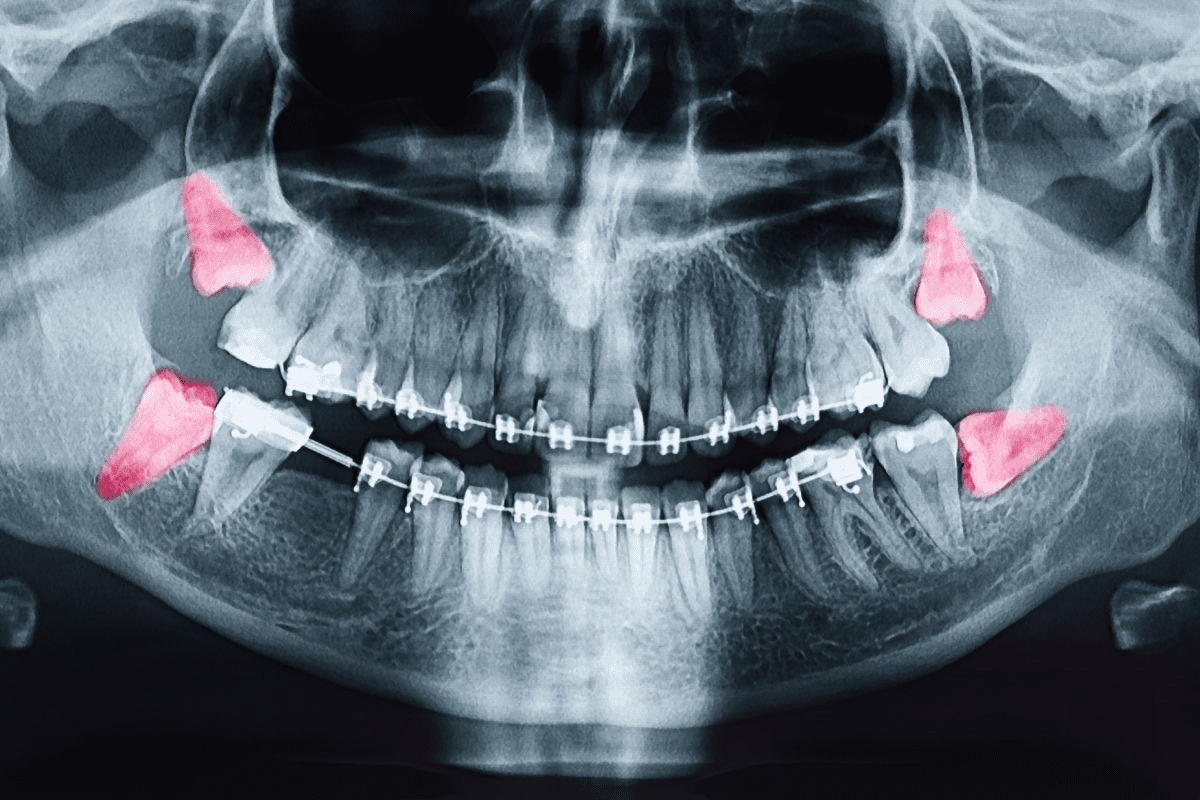

Odontogenic keratocysts are jaw cysts linked to tooth roots. They might not cause symptoms but can make the jaw bigger and could lead to breaks if not treated. Finding them early with X-rays is very important.

Imaging Methods

Imaging is very important for jaw tumor diagnosis. It gives us detailed info about the tumor’s size, location, and how far it has spread. We use:

- X-rays: Good for the first look, showing bone involvement.